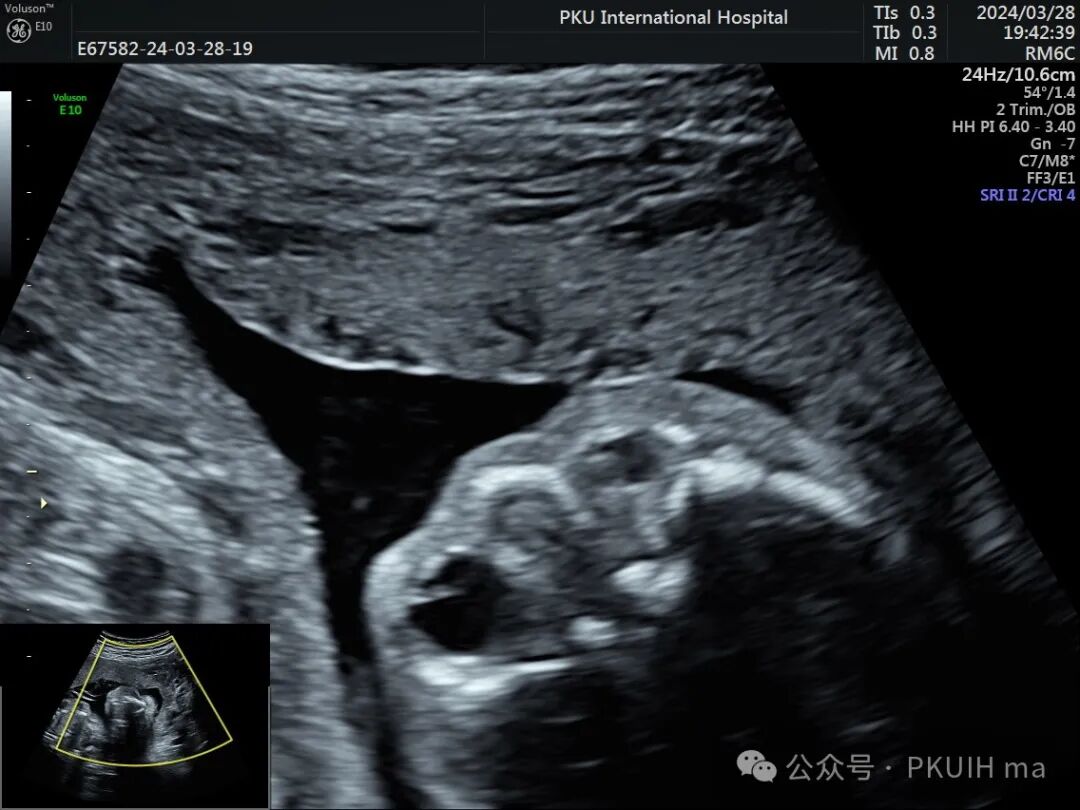

这个胎儿的眼睛怎么了?

今天来看一个胎儿,在大排畸检查时发现

右眼框、右眼球发育小,晶状体发育也很小

右眼晶状体后方见高回声区,其内未探及血流信号

左眼发育大小正常,但晶状体边缘增厚回声也增高,应该也是有问题

双眼球对比观察两眼球发育不对称,右眼明显发育小

实时动态观察双眼发育不对称,右眼小;两侧眼球内晶状体、玻璃体均可见,右侧晶状体小,晶状体后缘玻璃体内见不规则的高回声区。